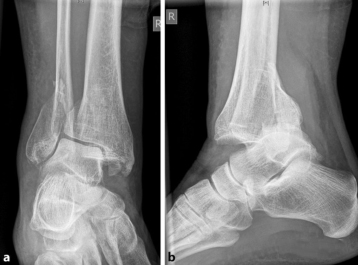

2024-04-24

Каковы факторы, вызывающие несостоятельность внутренней фиксации при лечении межвертельного перелома

Межвертельные переломы бедренной кости чаще встречаются у пожилых людей, чаще всего вызваны травмой, причем возраст ···

узнать больше